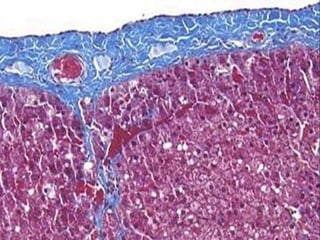

• #10 In the section of equine liver below (Masson's trichrome stain), the capsule and septae are stained blue , while hepatocytes are magenta . Notice how the capsule extends as a septum into the liver about one-third of the way from left, immediately below a large capsular blood vessel.

• #11 In the section of equine liver below (Masson's trichrome stain), the capsule and septae are stained blue , while hepatocytes are magenta . Notice how the capsule extends as a septum into the liver about one-third of the way from left, immediately below a large capsular blood vessel.

• #13 In the section of equine liver below (Masson's trichrome stain), the capsule and septae are stained blue , while hepatocytes are magenta . Notice how the capsule extends as a septum into the liver about one-third of the way from left, immediately below a large capsular blood vessel.

Cápsula de Glisson Parênquima: Lâminas de hepatócitos Sinusóides Áreas portais: veia porta,  artéria hepática,  vasos linfáticos, ductos biliares e nervos